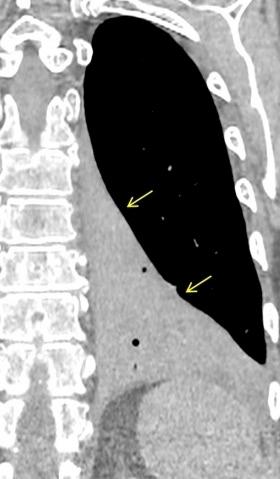

INFARTO PULMONAR EN TEP. Signos locales

Espinosa LA et al. Clinical utility of multiplanar reformation in pulmonary CT angiography. AJR 2010

INFARTO PULMONAR EN TEP. Frecuencia de signos

Borde convexo. 46% Lóbulos inferiores. 73%

Ápex “truncado” 57%

+ de 1 infarto. 33%

Base pleural ancha. 65%

74 pacientes: Infarto presente en 32%

< realce focal parenquimatoso. 95%

Vaso grueso hacia ápex. 14%

Radiotransparencias internas. 32% Tractos densos hacia el hilio. 24%

He H et al. Pulmonary infarction: spectrum of findings on multidetector helical CT. J Thorac Imaging. 2006